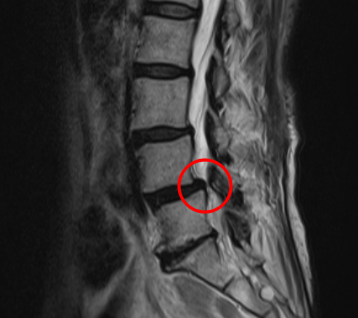

治療前

腰椎MRIを確認したところ、赤い枠で示されているL4/5に部分に脊柱管狭窄症を認めました。またこの腰部脊柱管狭窄症は、腰部すべり症が原因であると考えられます。